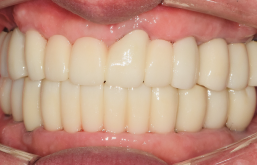

꼼꼼한 진료로 만족스러운 치료결과를 만들어드립니다.